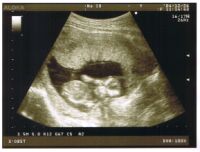

4ヶ月(13w1d) 検診

今日のぱっくんは 7.5cm になってました。手を目のところに当ててる写真なんですが、わかるでしょうか? 超音波の写真ってどこがどうなってるか説明してもらわないとなかなかわからないんですよね〜。今日の会計は 2500円。超音波を見るだけだと このくらいの金額なんでしょうか。。